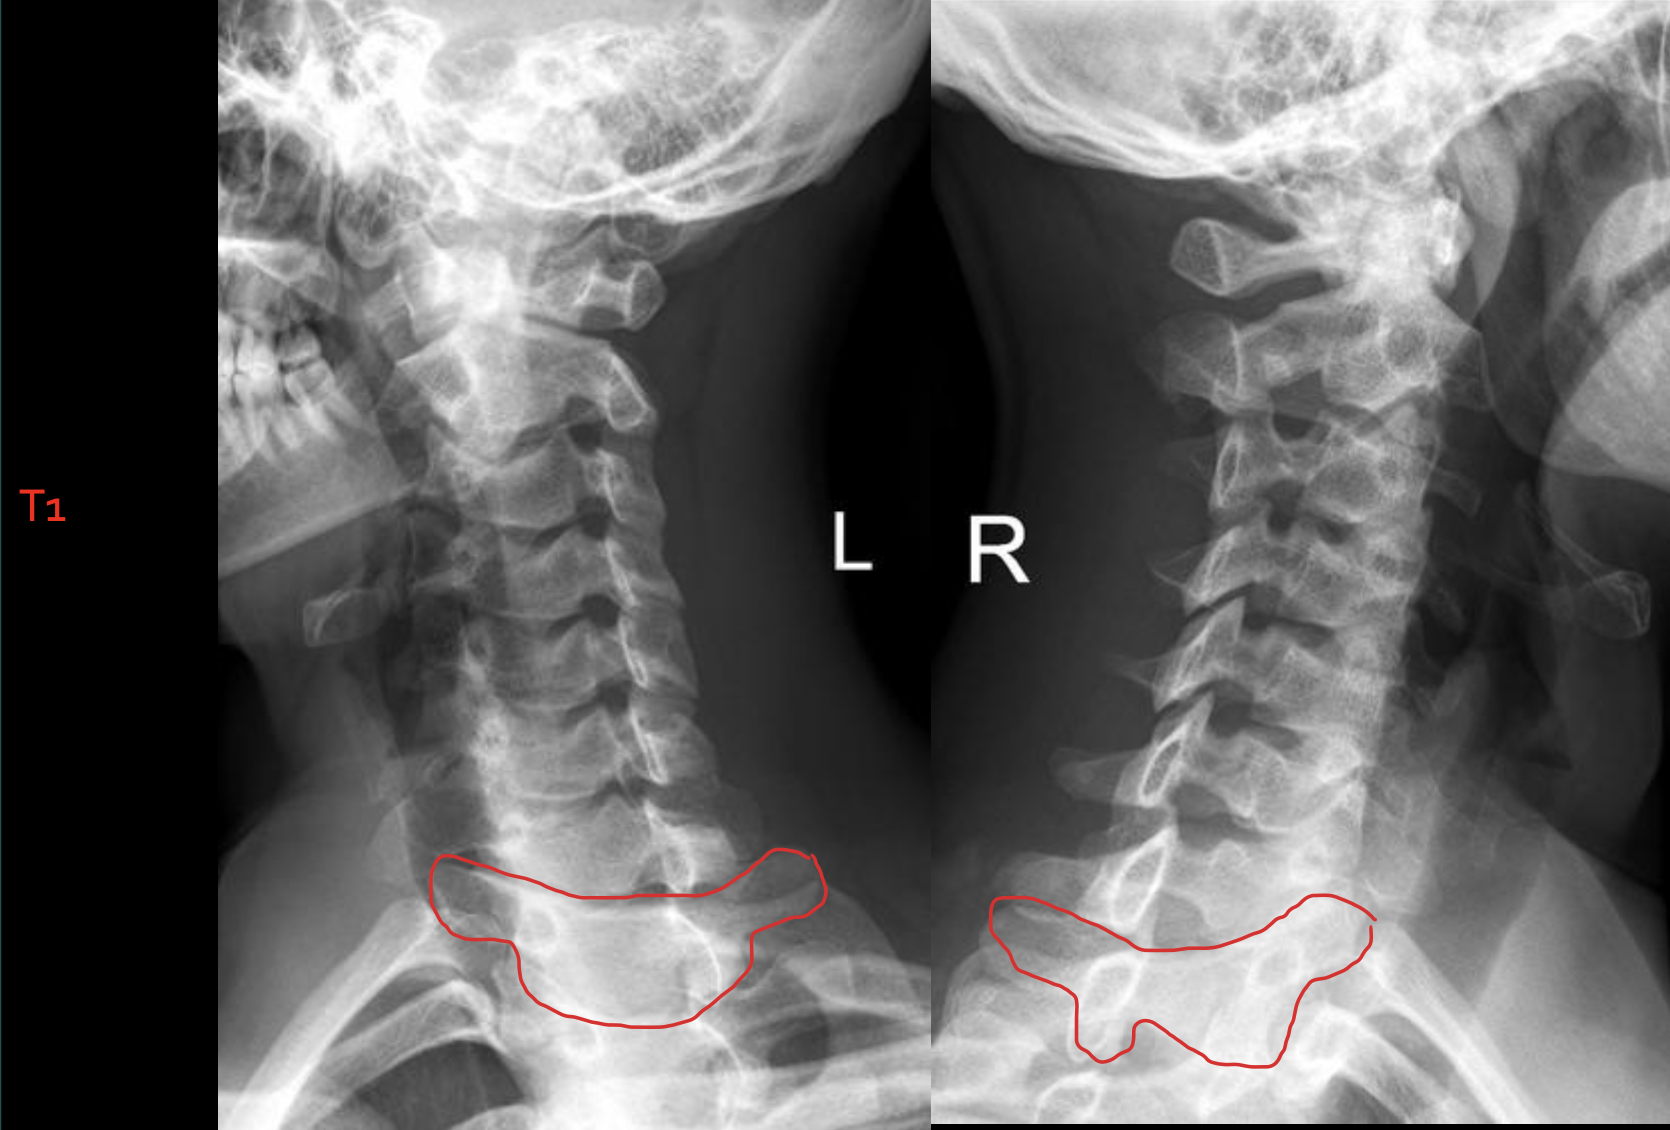

T1